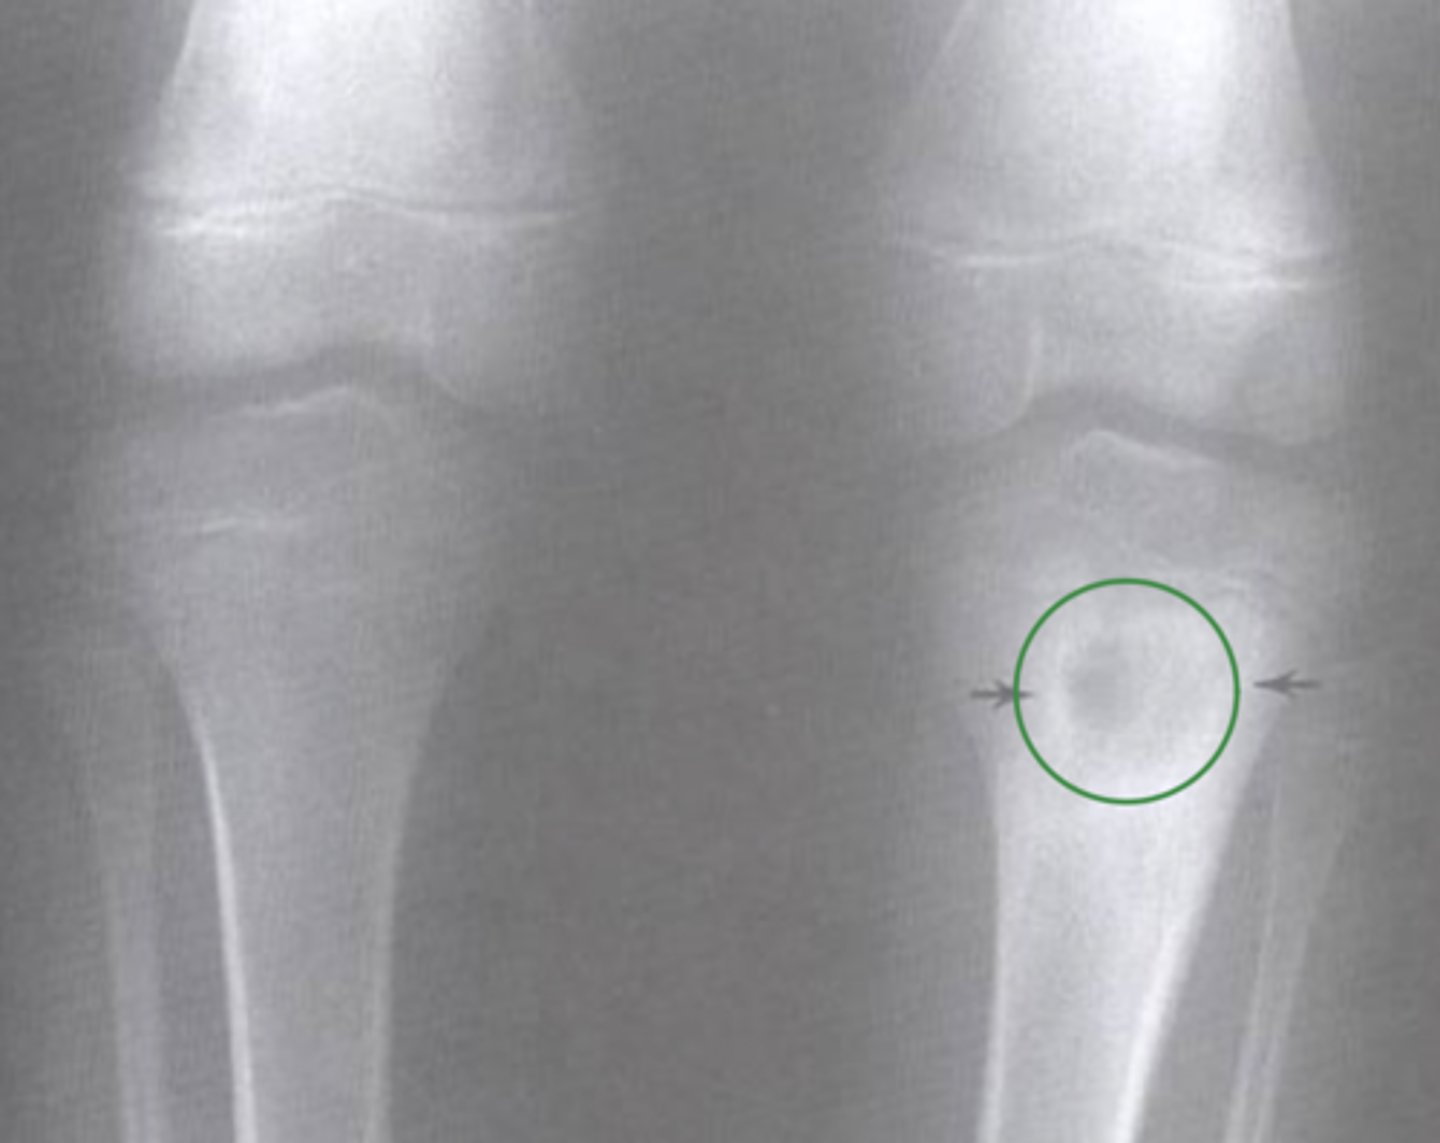

Bilateral AP of knees

What view does this show?